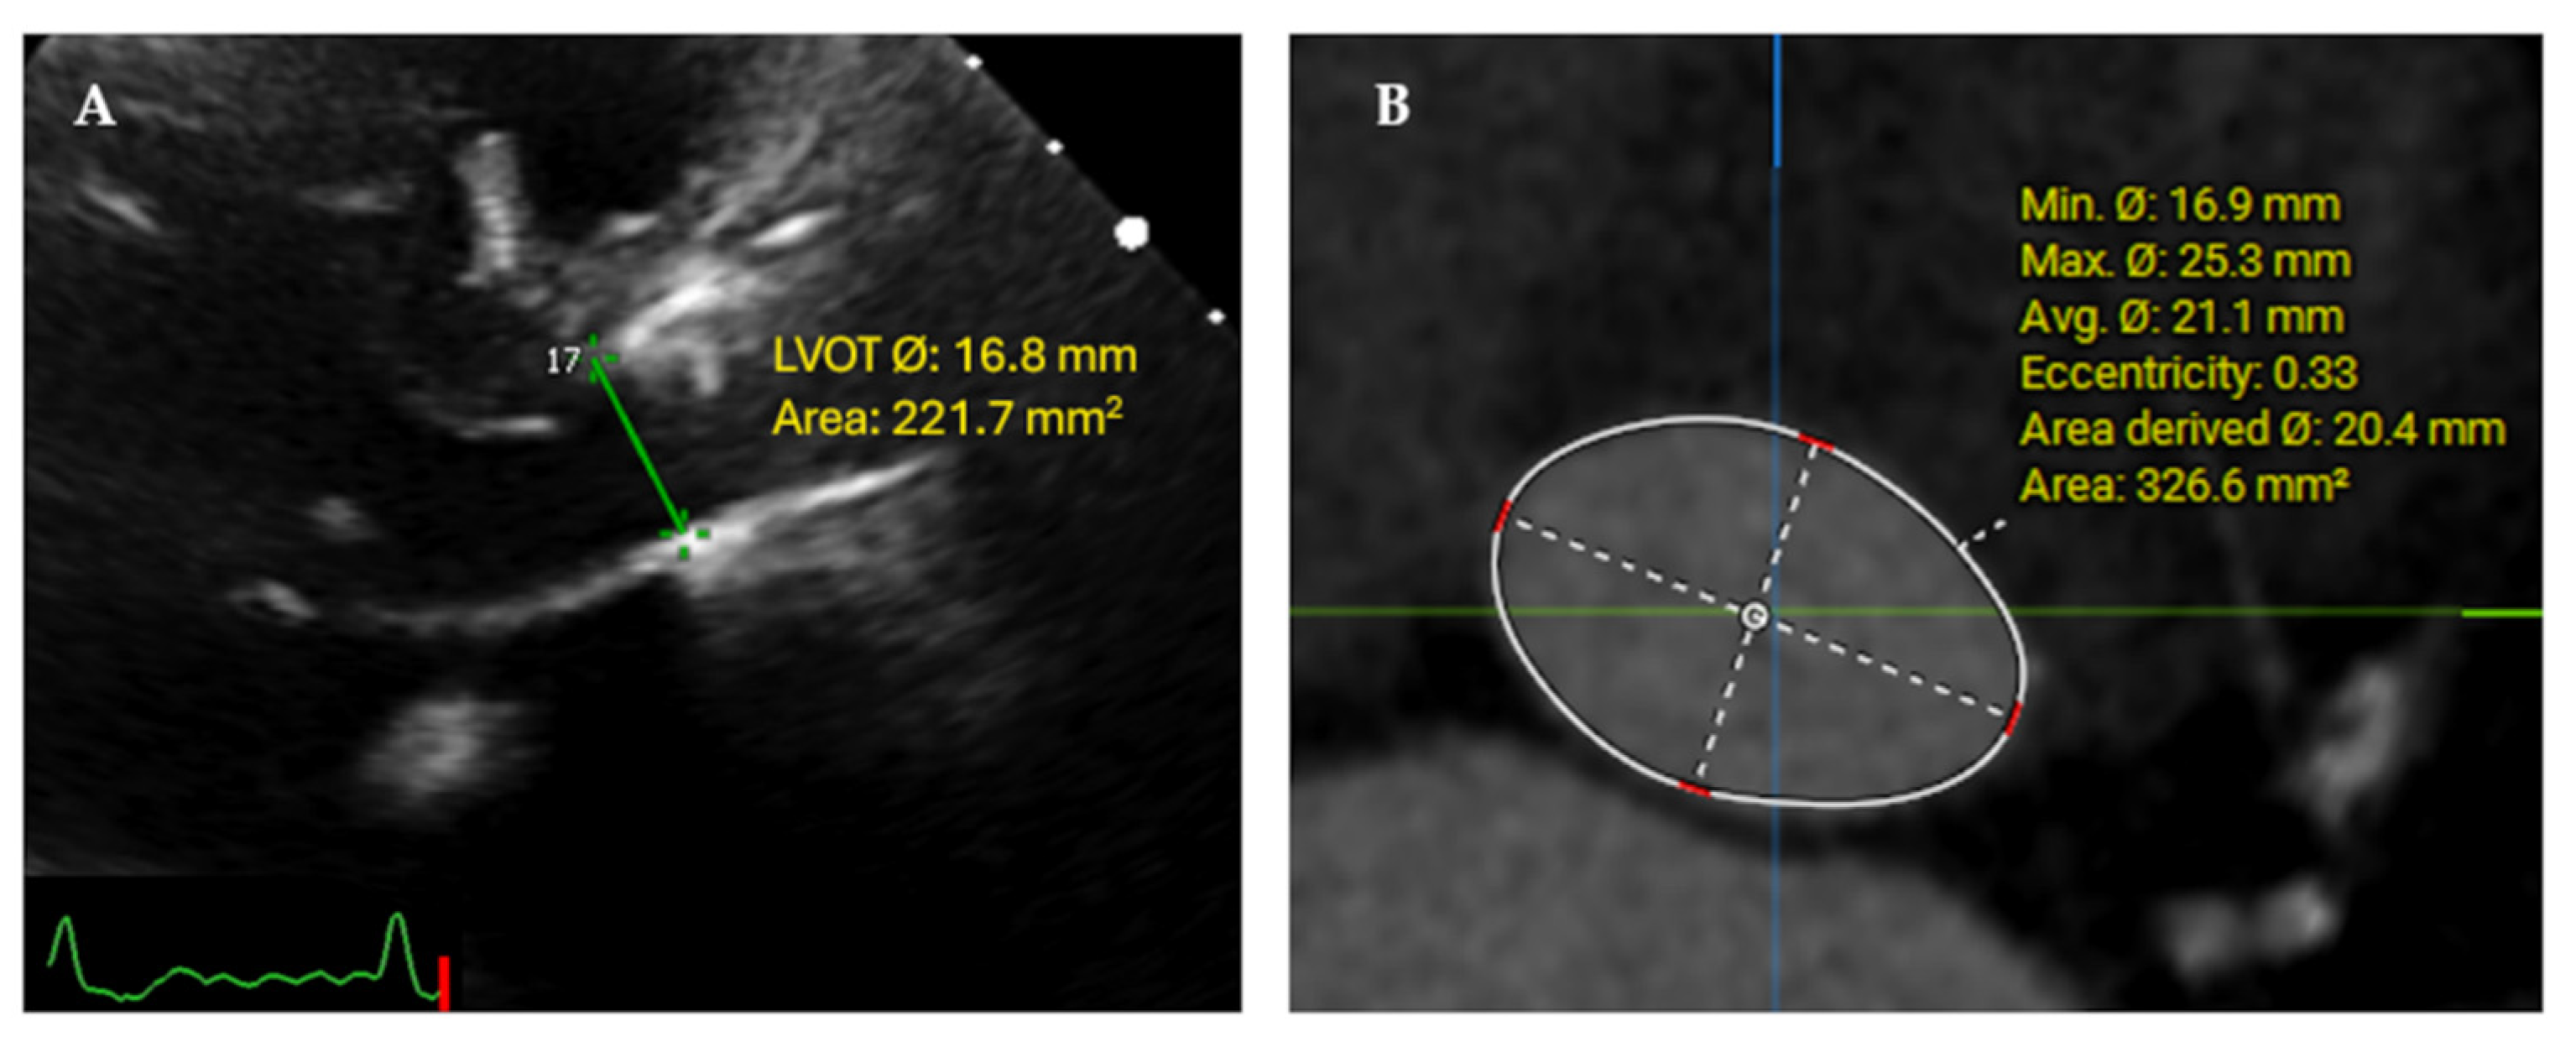

2.3. Multidetector Computerized Tomography (MDCT)

| MDCT-derived LVOT measurements | |

|      Minimum diameter, mm Maximum diameter, mm LVOT area, mm2  | 19.03 (2.55) 26.92 (2.43) 405.22 (81.32)  |

| LVOT diameter, mm | 21.03 (1.9)  | Minimum diameter 19.03 (2.55) | [1.7, 2.31] |

| Maximum diameter 26.92 (2.43) | [−6.2, −5.58] | ||

| LVOT area, mm2 | 350.4 (62.04) | 405.22 (81.32) | [−55.15, −36.09] |